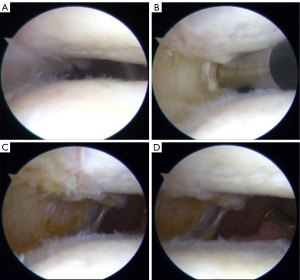

All surgical procedures were performed by the same surgeon (ML) with the patients in a supine position under general anesthesia. All patients underwent a careful, routine arthroscopic inspection and evaluation of the meniscus, ligaments, and articular cartilage and appropriate management if necessary. The anterolateral portal was routinely used to establish the inspection channel (Figure 2A), and the anteromedial portal was used to establish the operation channel. First, the hypertrophic inflammatory synovial tissue and synovial folds were removed. In patients with LRR, with the aid of an arthroscopic radiofrequency knife, LRR was completed from the distal to the proximal pole of the lateral border of the patella. The released soft tissue included the superficial and deep layers of the joint capsule and retinaculum (Figure 2B,2C). LRR was considered satisfactory when the joint space between the lateral patella and trochlea was enlarged and symmetrically distributed (Figure 2D).